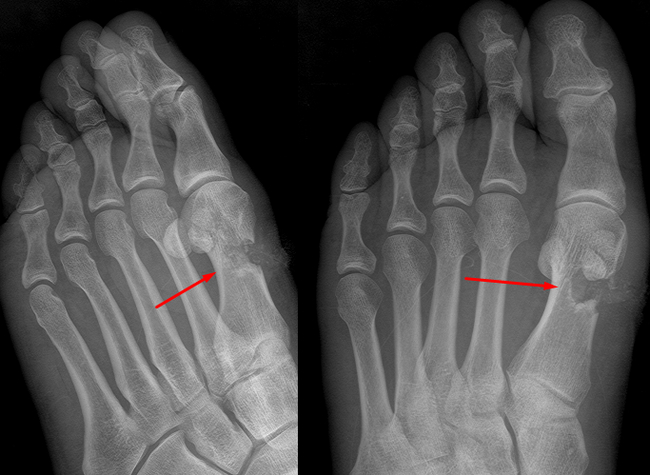

Планово для МСЭ обследовали мужчину, которому в 1983 г. в пьяной драке выстрелили из ружья в левое плечо. Плечевая кость была сломана выстрелом, перебеты все нервы (до сих пор не двигаются пальцы на руке, плохо гнется рука в плечевом суставе. Сформировался лодный сустав (т.е. кость не срослась вообще). Кость деформировна. В проекции перелома множественные металлические осколки дроби.